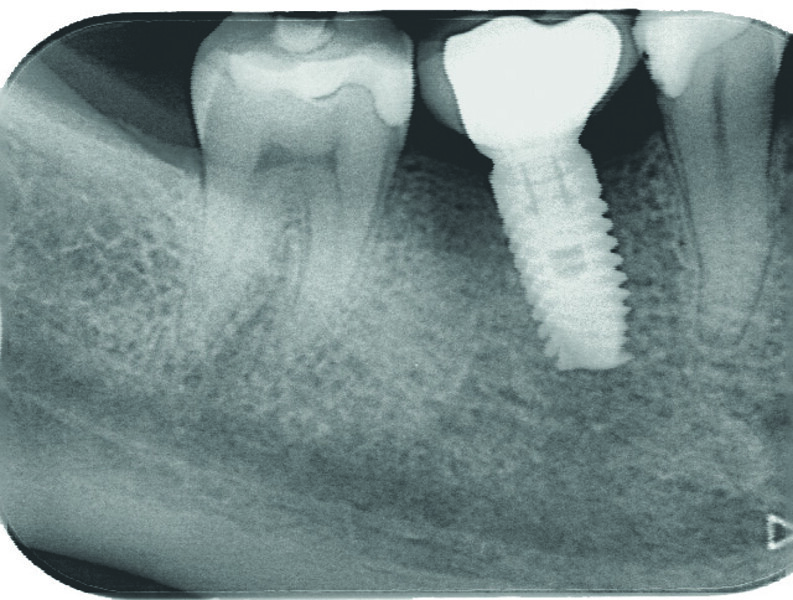

Examen clinique et radiologique L’examen clinique et radiographique met en évidence la possibilité de poser un implant (Figs. 1 et 2).

Fig. 1 : Radio panoramique, on visualise bien le secteur édenté en 46.